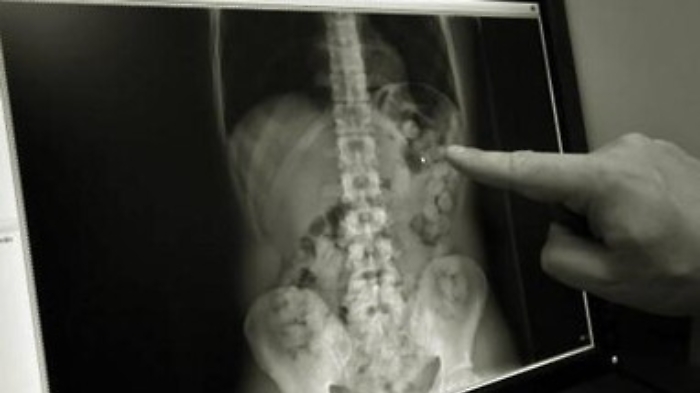

La presenza nel suo stomaco dei 40 grammi di eroina che, se opportunamente tagliata, avrebbe consentito di ricavare circa 100 dosi, è stata accertata durante una radiografia alla quale è stato sottoposto nell’ospedale di Ragusa. L’arrestato, su disposizione del pm Giulia Bisello, è stato rinchiuso nel carcere di Ragusa.